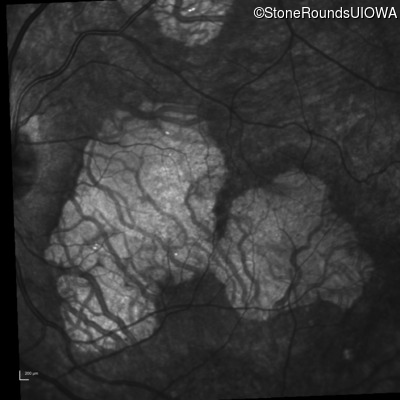

Infrared Fundus Photograph - Right - 20/20 -2 sc

Exemplar